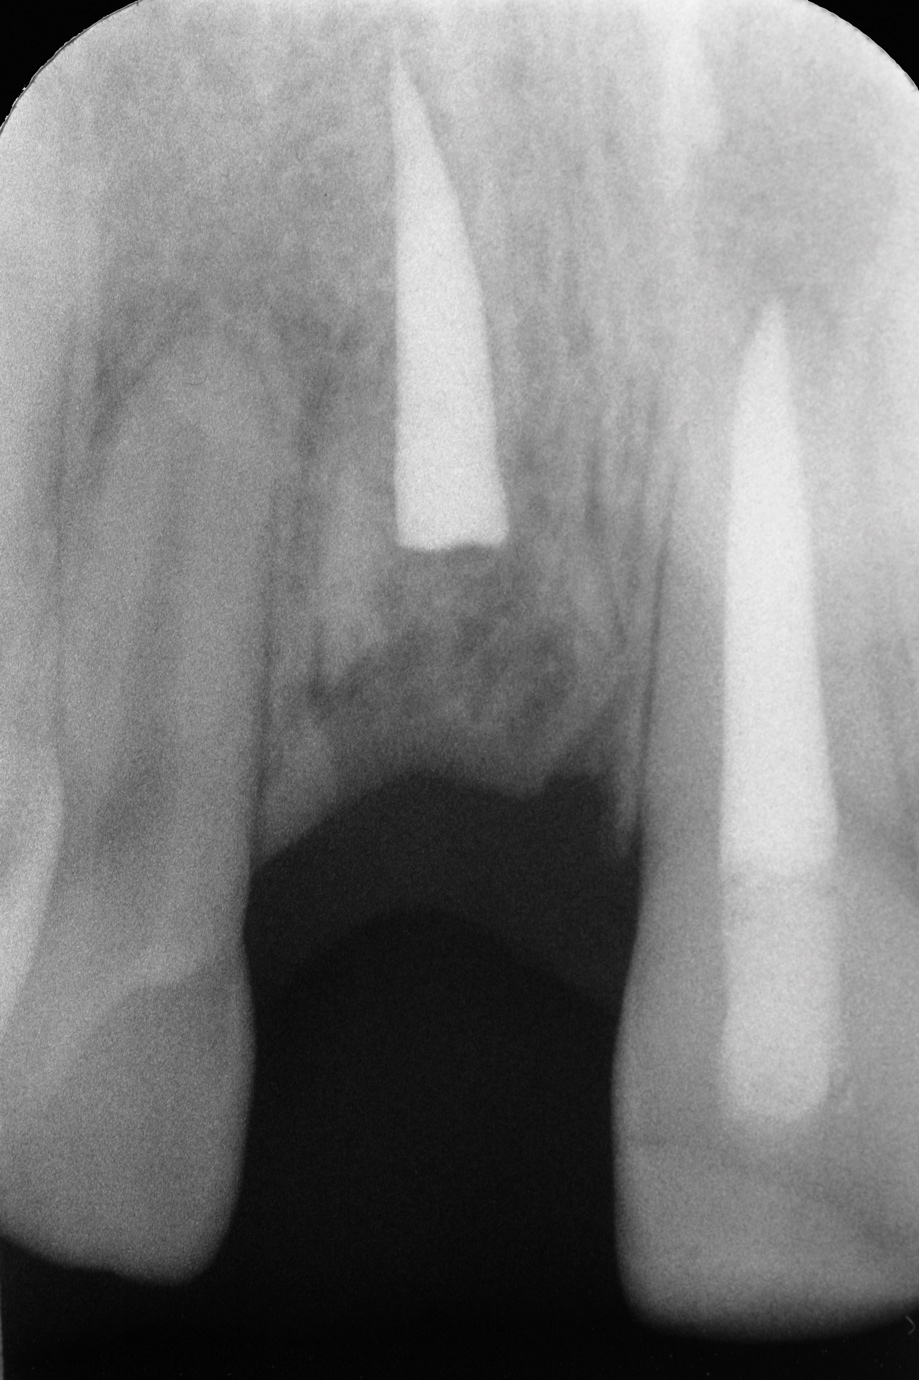

Fig 12. Age 9. Radiograph of teeth Nos. 8 and 9 at initial examination. Orthodontic brackets were placed to stabilize the teeth.

Figure 12

Teeth Nos. 7 through 10 were included in the endodontic examination. Nos. 7 and 10 responded to cold; there was no response to cold or electric pulp test (EPT) from either tooth No. 8 or 9. All the teeth gave a mild positive response to percussion, and none of the teeth were tender to palpation. Both Nos. 8 and 9 probed within normal limits (WNL). Radiographs showed a small apical radiolucency associated with No. 8 and a widened periodontal ligament (PDL) on the mesial and apical aspect of No. 9 (Figure 12). An access was made in No. 8, and the canal was debrided and filled with Ca(OH)2.

One month later, the teeth were reevaluated. Nos. 7 and 10 continued to respond to cold. No. 8 was not mobile and sounded ankylosed when percussed. No. 9 was slightly mobile and did not respond to cold or EPT. A 3 mm x 3 mm apical lesion had formed on No. 9. Ca(OH)2 was replaced in tooth No. 8, and No. 9 was opened, debrided, and filled with Ca(OH)2. Both teeth were filled with gutta-percha 6 months after the initial endodontic examination. At that time, tooth No. 8 showed early evidence of replacement resorption on the mesial of the root; No. 9 was slightly mobile and the PDL appeared intact (Figure 13).

In 2006, Malmgren et al presented a hypothetical biological explanation for the maintenance of crestal bone labiopalatal width and the continued development of the vertical height of crestal bone after decoronation of ankylosed teeth.28 The article proposed that the development of the vertical height is related to skeletal jaw growth and tooth eruption. In the present case 2, a comparison of the root apices of teeth Nos. 7 and 8 at ages 9.5 and 14.5 years shows the amount of coronal ridge growth/eruption of No. 7 that occurred relative to ankylosed No. 8 beforedecoronation(Figure 13 and Figure 16). One year after decoronation, the apices of teeth Nos. 7 and 9 did not appear to have moved coronally relative to their location before surgery (Figure 16 and Figure 17).